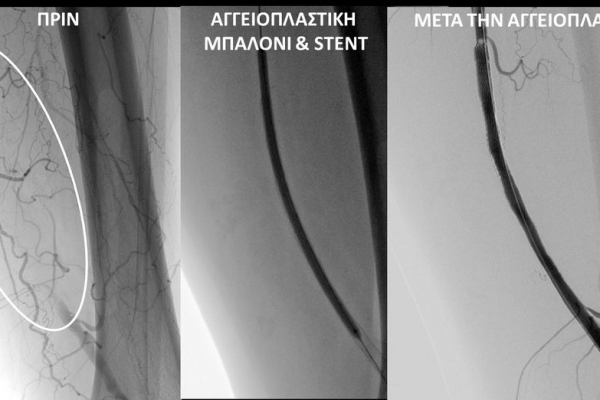

O σακχαρώδης διαβήτης είναι μεταβολική ασθένεια η οποία χαρακτηρίζεται από αύξηση της συγκέντρωσης του σακχάρου στο αίμα (υπεργλυκαιμία) και διαταραχή του μεταβολισμού της γλυκόζης. Ο βαθμός αύξησης της γλυκόζης στο αίμα και η παραμονή των αυξημένων τιμών της για μεγάλο χρονικό διάστημα βλάπτουν, κυρίως, τα μικρά αγγεία, προκαλώντας διαβητική νευροπάθεια, διαβητική νεφροπάθεια, αμφιβληστροειδοπάθεια κ.τ.λ., με σοβαρότατες συνέπειες σε πολλά όργανα-συστήματα.Στην Ελλάδα κάθε χρόνο πραγματοποιούνται 2.000 – 3.000 ακρωτηριασμοί κάτω άκρων, αφού το 4-5% των πασχόντων από διαβήτη εμφανίζει περιφερική αγγειοπάθεια με έλκη ή και γάγγραινα στα πόδια. Σε ποσοστό 80% οι ακρωτηριασμοί θα μπορούσαν να αποφευχθούν και η επεμβατική ακτινολογία μπορεί να βοηθήσει σημαντικά.Η διαδερμική ενδαγγειακή αγγειοπλαστική (percutaneous transluminal angioplasty, PTA) είναι μια ελάχιστα επεμβατική μέθοδος αντιμετώπισης των αρτηριακών στενώσεων ή και αποφράξεων του διαβητικού ποδιού (περιφερικήδιαβητικήαρτηριοπάθεια).